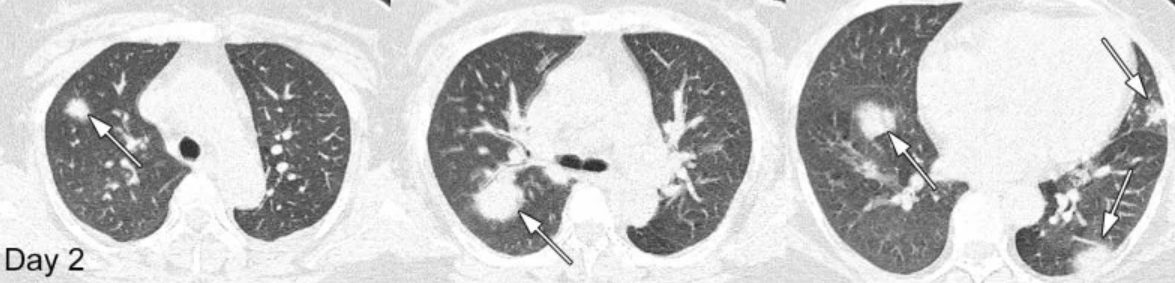

Медицинские снимки людей, страдающих КОВИД-19, вызванной SARS-CoV-2, показывают, как это заболевание влияет на легкие пациентов. КТ-сканирование стало "первой линией защиты" в диагностике подозрительных инфекций, особенно учитывая текущую нехватку тест-наборов, по данным Рентгенологического общества Северной Америки (RSNA), которое опубликовало серию снимков в нескольких научных работах. Кардиоторакальная томография, которая описывает случай 44-летнего мужчины, который был сотрудником транспортной службы на рынке морепродуктов Хуанани в Ухане, Китай, который, как полагают, является местом возникновения вспышки. Мужчина страдал от высокой температуры и кашля в течение 13 дней, когда был госпитализирован 25 декабря 2019 года. Там ему поставили диагноз - тяжелая пневмония - состояние, характеризующееся воспалением воздушных пространств в легких и острым респираторным дистресс-синдромом, согласно исследованию. В конце концов, врачи поставили ему диагноз КОВИД-2019, исключив инфекцию друг

Мужчина страдал от высокой температуры и кашля в течение 13 дней, когда был госпитализирован 25 декабря 2019 года. Там ему поставили диагноз - тяжелая пневмония - состояние, характеризующееся воспалением воздушных пространств в легких и острым респираторным дистресс-синдромом, согласно исследованию.

В конце концов, врачи поставили ему диагноз КОВИД-2019, исключив инфекцию другими патогенными микроорганизмами, которая может привести к пневмонии. Несмотря на усилия по его спасению, человек, к сожалению, умер примерно через неделю.

"Этот случай, произошедший при эпицентральной вспышке КОВИД-19 пневмонии, иллюстрирует потенциальную тяжесть этого заболевания, в то же время подчеркивая роль визуализации для мониторинга прогрессирования болезни",

"Более того, компьютерная томография может также играть важную диагностическую роль, особенно при отсутствии подтверждающих тестов".

На КТ легких отчетливо видны белые пятна. Обычно это признак аномалии, которую рентгенологи называют "помутнением стекла" - или частичным заполнением воздушных пространств в легких.

Помутнение также можно увидеть на КТ легких 54-летней женщины из Вухана, которая также заразилась новым коронавирусом, известным и атипичной пневмонией (SARS-CoV-2). Однако, в отличие от предыдущего случая, эта женщина выжила. Сканирование, проведенное после нескольких дней поддерживающего и противовирусного лечения, показало значительное улучшение степени и плотности помутнения грунтового стекла.